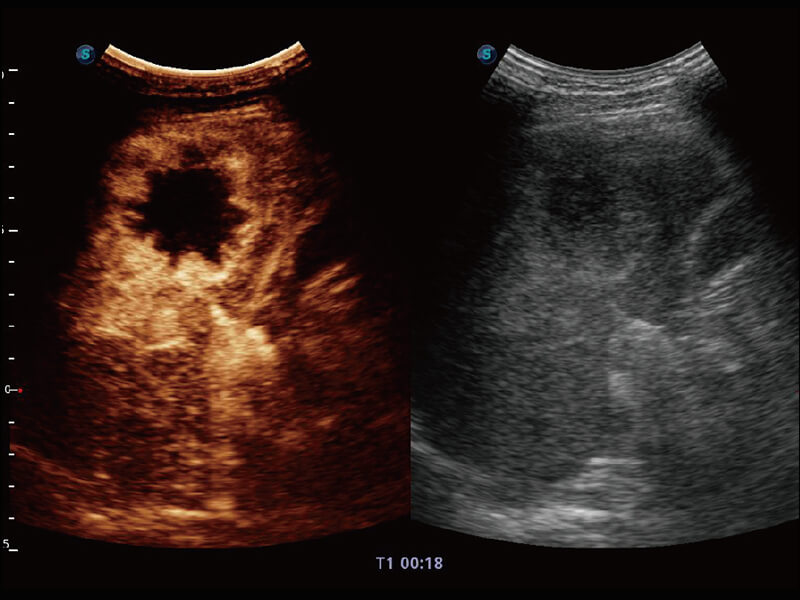

S60探头工艺,从前端信号处理每一个环节采集无损声学数据,真实还原组织原貌,再现解剖细节。

超宽频带技术,为容积成像带来优质的二维图像基础,为您呈现丰富的结构细节,栩栩如生地展示宝宝的宫内形态以及各种组织的立体结构。